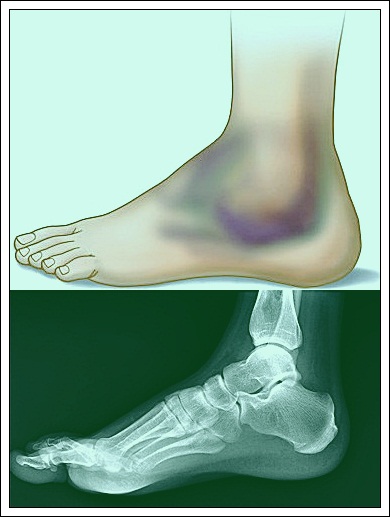

Broken foot refers to a fracture or cracks in any of the foot bones. In most cases, the region around the fracture becomes tender and bruises may also appear. It is important that one should not place any weight on such a foot until it has been assessed by a doctor and proper treatment given.

Symptoms of broken foot

Broken bones result in swelling and severe pain on the foot. The pain is often too much that a person cannot walk. However, if the break is in the toe, the pain is usually less and one can even walk. Bruises are common on the broken bone. It should be noted that sprains can also lead to severe pain hence it is not all swelling, pain, and bruising that suggests a broken bone.